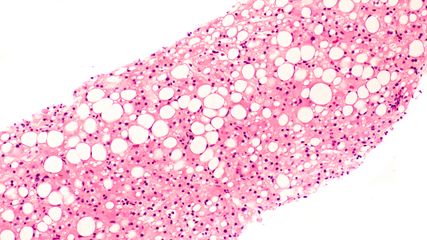

Die Diagnose MASLD wird gestellt, wenn eine hepatische Steatose zusammen mit mindestens einem von fünf kardiometabolischen Risikofaktoren vorliegt. Diese sind: Übergewicht, Typ-2-Diabetes, Bluthochdruck, erhöhte Plasma-Triglyzeride und niedriges HDL-Cholesterin.2 Die Definition wurde 2023 zusammen mit der Bezeichnung «MASLD» in einem globalen Prozess erarbeitet, bei dem Hepatologie- und Endokrinologiegesellschaften sowie Patientenorganisationen aus 56 Ländern beteiligt waren. «MASLD» löste den bisherigen Begriff der «nichtalkoholischen Fettlebererkrankung» (NAFLD) ab. Diese Bezeichnung war mit Einschränkungen behaftet. So zum Beispiel wurde die eigentliche Ursache der Erkrankung nicht anerkannt. Zudem war die Wortwahl für Betroffene potenziell stigmatisierend.3

Semela stellte zu Beginn seines Vortrags einen Patienten vor, der die Kriterien einer MASLD erfüllte: Der 63-Jährige war übergewichtig, hatte einen Typ-2-Diabetes, eine Dyslipidämie und Bluthochdruck. Die Leberbiopsie zeigte eine Fibrose und 40% Steatose. Nebst den erhöhten Lipid- und Blutglukosewerten waren entsprechend auch die Leberenzyme ausserhalb der Norm. «Aufgrund des Diabetes erhielt der Patient dann Semaglutid», sagte Semela und machte damit den Einstieg in seine Präsentation der fünf Therapien bei MASLD.